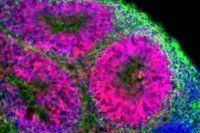

Snapshot

Pigment-Producing Skin Cells Generated Using Stem Cell Technology

Memorial Sloan Kettering researchers have developed innovative ways to study some skin diseases, including melanoma skin cancer.